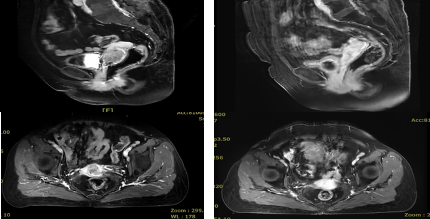

注:图A、B为放疗前MR,病变约40×58mm,图C、D为放疗后1月MR,病变完全消失。